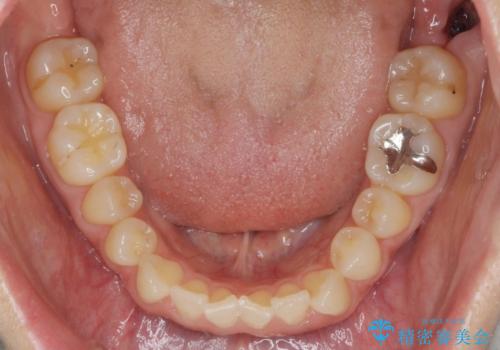

前歯の目立つガタつきをマウスピース矯正で治療

- 大きく傾いてしまった前歯のガタつきの改善を求めて来院されました。

前歯のガタつきをしっかりと取り、機能的・審美的に理想的な歯並びをマウスピース矯正で達成します。

強度のガタつきはマウスピース単体では並び切ることが難しいこともありますが、しっかりと装着していただいたことで良好な治療結果を得ることができました。